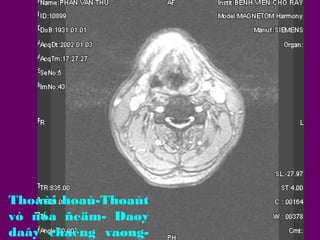

Thoaùi hoaù-Thoaùt

vò ñóa ñeäm- Daøy

daây chaèng vaøng-

Thoaùt vò ñóa ñeäm

Thoaùt vò ñóa ñeäm daïng m